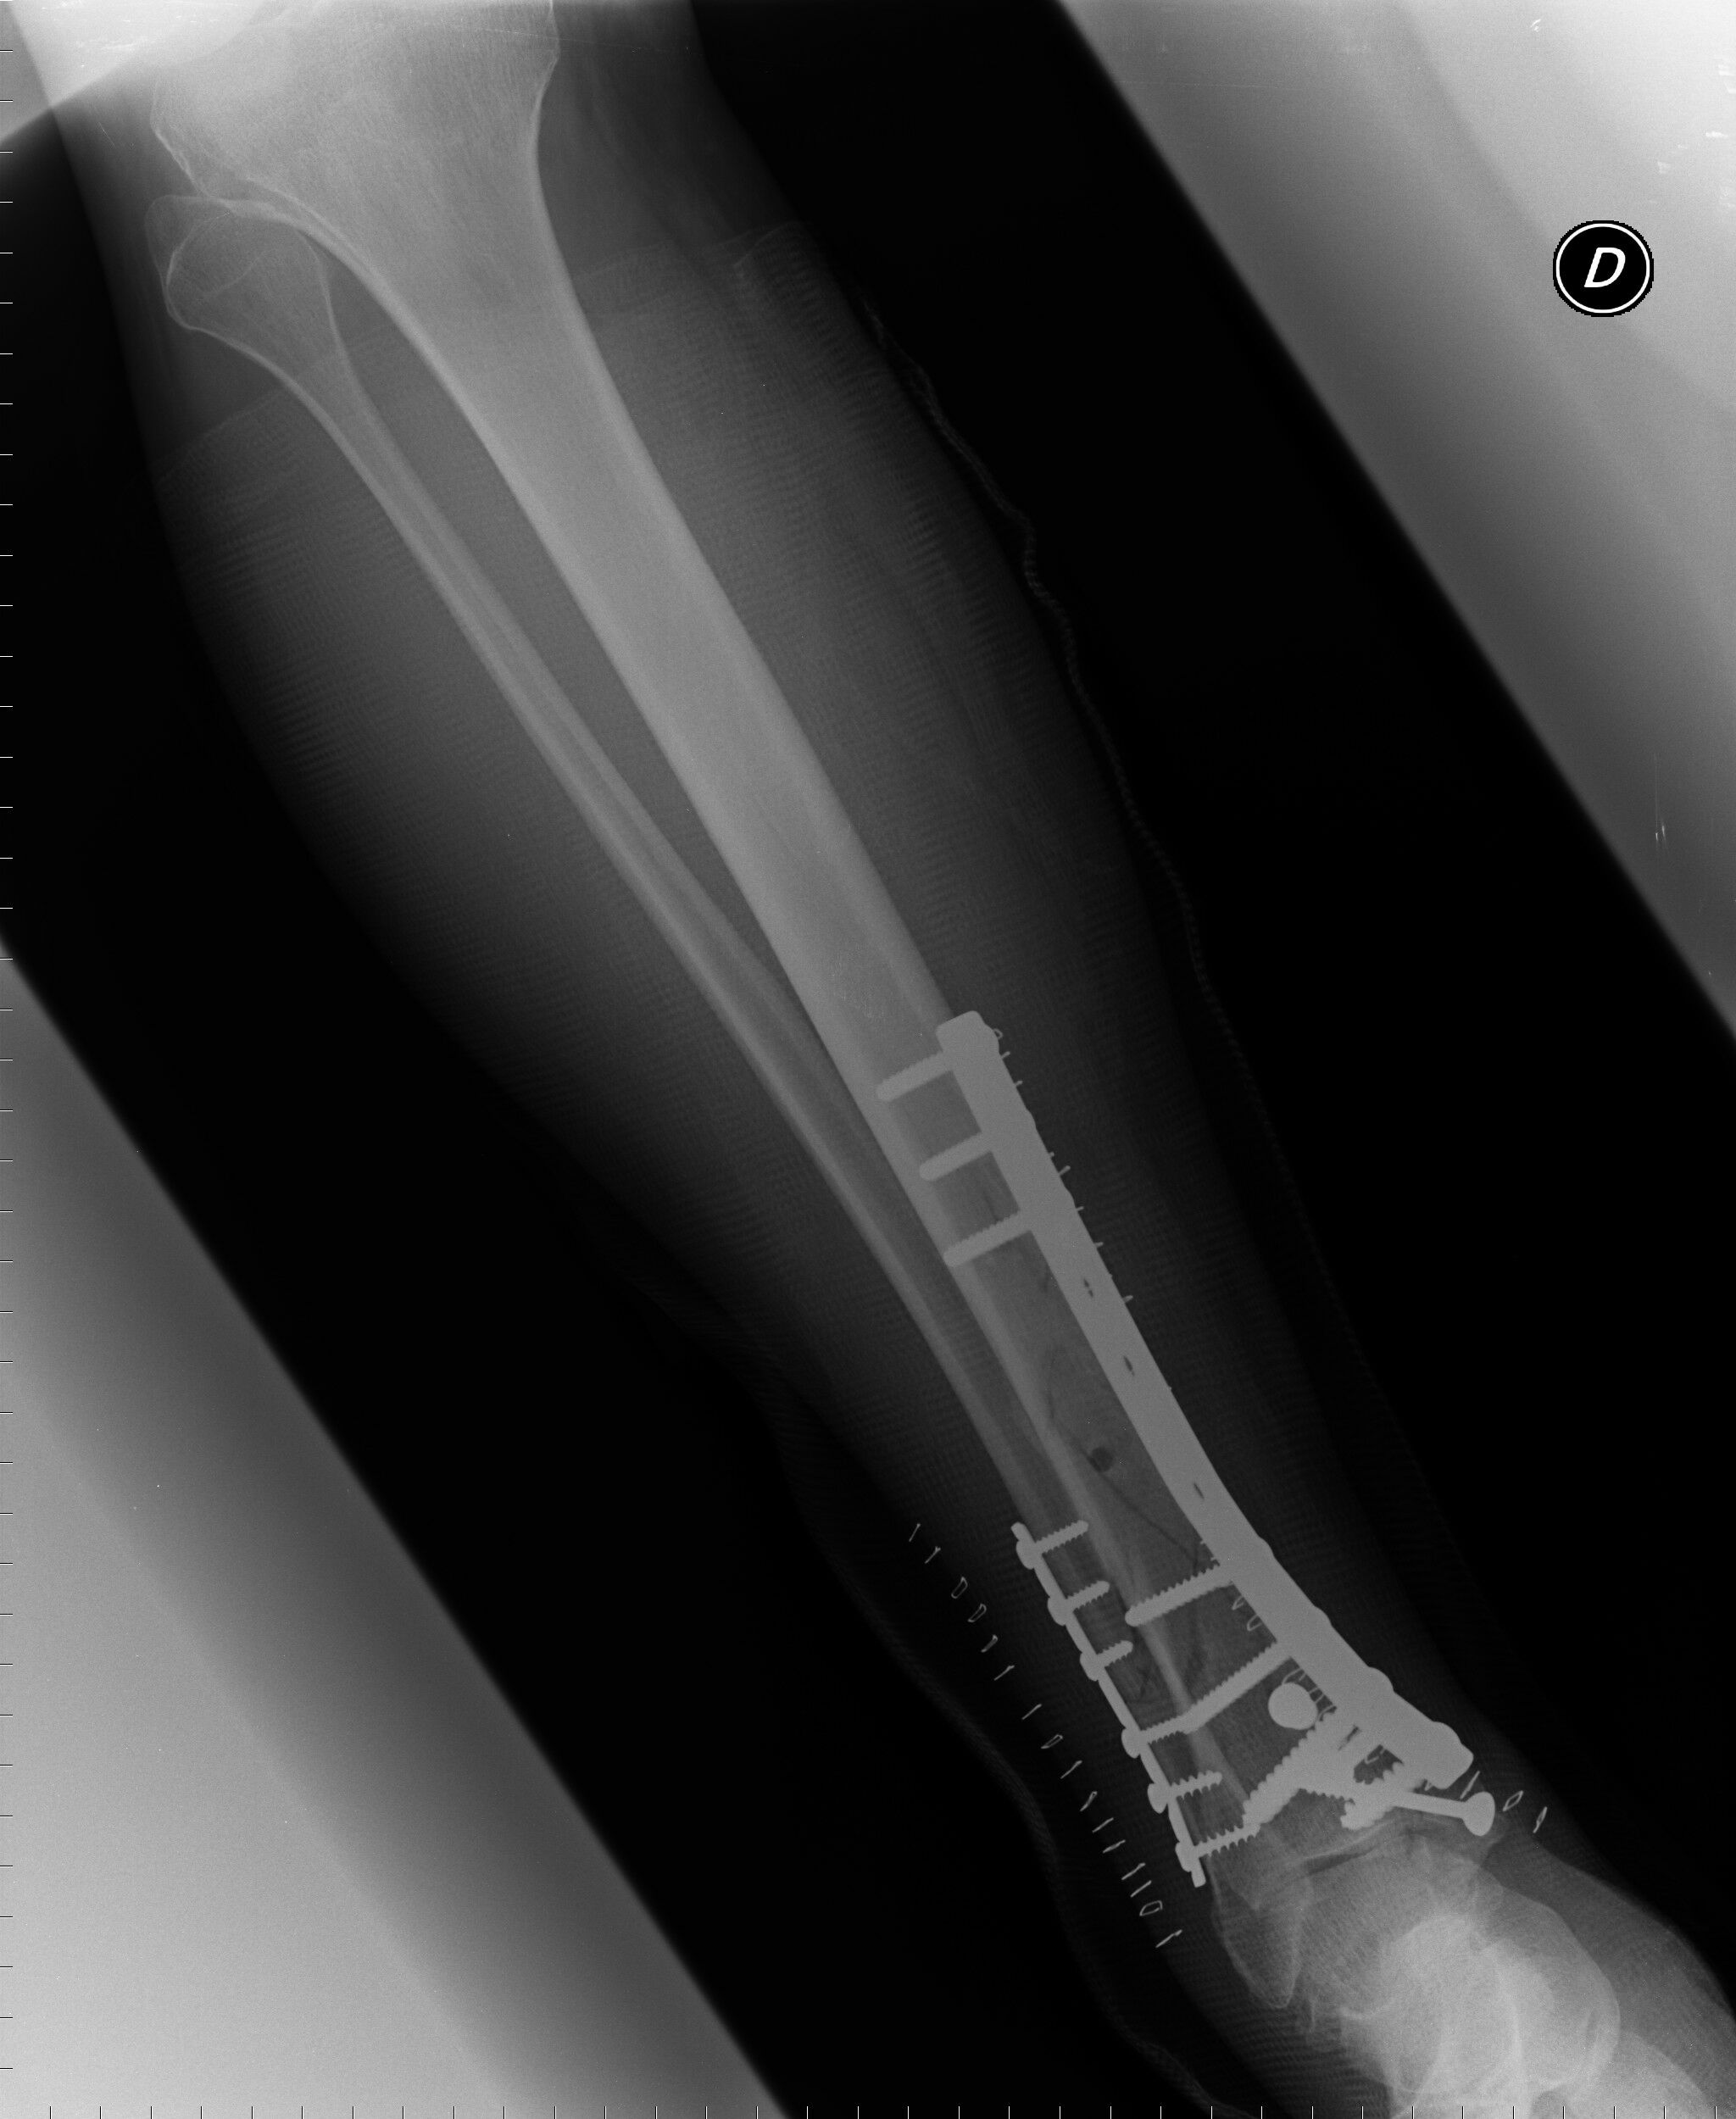

6. Dnes mi ortoped v Prostějově řekl,že je to mistrovská práce,že to nedělal ortoped,ale umělec. Jinak,příští rok se pokusím dojet domů bez pomoci sanitky.Mimochodem,v kůlně nestojí,ale v teple doma. A nestojí ani v šopě!!!!! Źe Bobe

8. Pokud správně počítám,tak 15. Ale řekl bych ,brilantní práce.

9. Kdyby měl případný místní ortoped zájem o foto výsledku italských chirurgů,tak sem dám fotku.